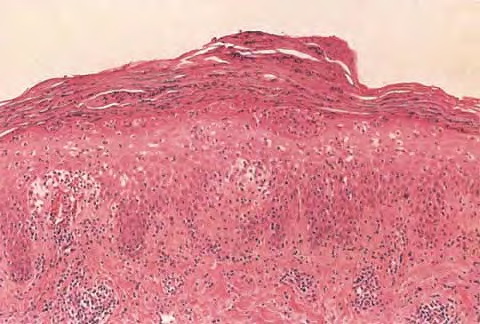

Morphea profundus =صلابة الجلد العميقة

Morphea profundus =صلابة الجلد العميقة Morphea In morphea, or circumscribed scleroderma, the lesions usually are limited to the skin and to the subcutaneous tissue beneath the cutaneous lesions. Occasionally, however, the underlying muscles and rarely the underlying bones are also affected. Morphea may be divided according to morphology and distribution of lesions into six types: […]